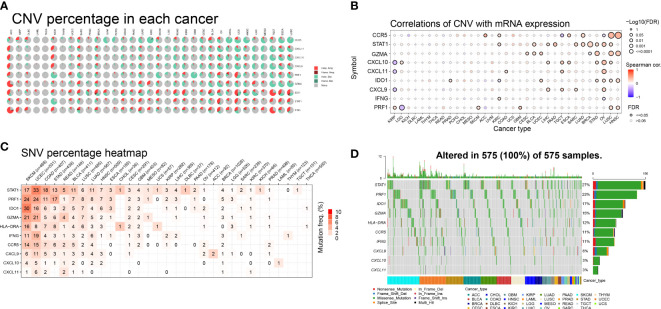

To investigate the impact of gene mutations on gene expression, we analyzed the mutation status of IFN-γ-related genes in different tumors. Our study examined the genetic variations of genes associated with IFN-γ in 33 distinct cancers and found that in most malignancies, these genes were associated with copy number variation (CNV). Among the 9 genes we investigated, heterozygous amplification and heterozygous deletion were the most common mutations observed in the 33 distinct cancers. Specifically, heterozygous amplification was the most prevalent CNV type in IDO1, STAT1, and IFNG, while heterozygous deletion was the main CNV type for CCR5, CXCL11, CXCL10, CXCL9, PRF1, and GZMA across 25 tumors. Additionally, in cases of adrenocortical carcinoma (ACC), heterozygous amplification was the primary type of CNV (f2).

Furthermore, we conducted additional research to explore the relationship between relative linear copy number values and the mRNA expression levels of genes associated with IFN-γ. Our data revealed a strong positive correlation between the expression of CCR5, GZMA, IDO1, and PRF1 and CNV in both lung squamous cell carcinoma (LUSC) and head and neck squamous cell carcinoma (HNSC). Conversely, we observed a strong negative correlation between the expression of CXCL9, CXCL10, and CXCL11 and CNV in kidney renal papillary cell carcinoma (KIRP), which is a significant finding (f2). Additionally, we found a strong and favorable correlation between the expression of STAT1 and CNV.

We examined the mutations and types of variation in IFN-γ-related genes in each cancer type and discovered that uterine corpus endometrial carcinoma (UCEC) had the highest percentage (33%) of single nucleotide variations (SNVs) in STAT1, followed by skin cutaneous melanoma (SKCM), colon adenocarcinoma (COAD), stomach adenocarcinoma (STAD), rectum adenocarcinoma (READ), bladder urothelial carcinoma (BLCA), LUSC, and lung adenocarcinoma (LUAD). CASP1 had a high proportion of SNVs in UCEC, SKCM, LUSC, BLCA, and LUAD. In both SKCM and UCEC, the incidence of SNVs was higher in STAT1, PRF1, IDO1, GZMA, HLA-DRA, IFNG, and CCR5. The proportion of SNVs in CXCL10 and CXCL11 was lower (f2). These 10 genes mentioned above were the most common targets of missense mutations in pan-cancer single nucleotide polymorphisms (SNPs). The frequency of gene alterations was highest in patients with UCEC and SKCM, followed by those with STAD, COAD, BLCA, and pancreatic adenocarcinoma (PAAD). STAT1 had the highest proportion of SNPs (27%), followed by PRF1 (23%), IDO1 (17%), and GZMA (15%) (f2). These findings suggest that IFN-γ-related genes have a high frequency of mutations in various tumors and have the potential to be targeted further as therapeutic molecules.